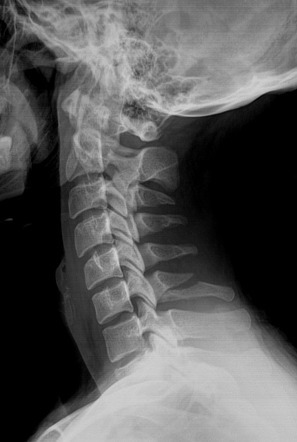

Q

Describe this fracture?

A

CLAY SHOVELER

- Fracture of the tip of the spinous process of the sixth or seventh cervical vertebra